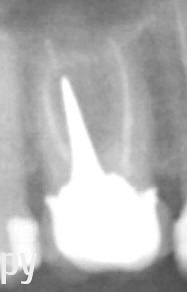

gsp Опубликовано 26 мая, 2014 Автор Поделиться Опубликовано 26 мая, 2014 Так? Скажите пожалуйста - я везде читаю что кладки делаю многоногие, а тут одна нога - есть ли минусы? А возможно ли коронку доделать (композитом например). Мне эстетики скорее всего хватит, а вот риск для корня пугает. Ссылка на комментарий

Evikrol Опубликовано 26 мая, 2014 Поделиться Опубликовано 26 мая, 2014 Вкладка отличная, необходимости многоногой вкладки нет. По рентгеновскому снимку нарушения прилегания коронки нет, претензий нет. Ссылка на комментарий

Korel Опубликовано 26 мая, 2014 Поделиться Опубликовано 26 мая, 2014 Вкладка отличная, необходимости многоногой вкладки нет. По рентгеновскому снимку нарушения прилегания коронки нет, претензий нет. +1 Ссылка на комментарий